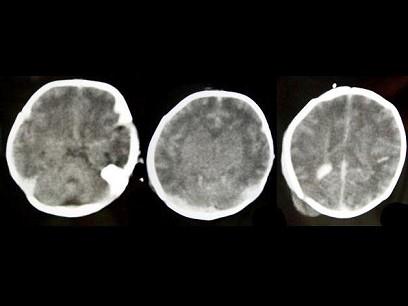

女,15天。吸吮反射减弱。CT检查,最可能的诊断为?(?)A.脑水肿B.新生儿缺氧缺血性脑病C.脑出血D.先天性无脑回E.先天性巨脑回

问题 女,15天。吸吮反射减弱。CT检查,最可能的诊断为?(?)

选项 A.脑水肿 B.新生儿缺氧缺血性脑病 C.脑出血 D.先天性无脑回 E.先天性巨脑回

答案 B